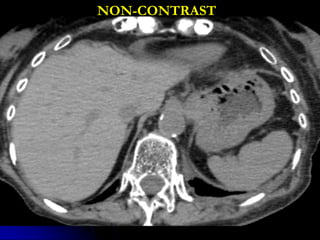

CT PROTOCOLS

• HEAD/CSPINE

• Non contrast

• 1mm acquisition, displayed thicker

• Coronal, sagittal reformats

• CHEST/ABD/PELVIS/TSP/LSP

• IV contrast

• Systemic arterial phase chest/upper abd

• Portal venous phase abd/pelvis

• Delayed phase upper abd

NON-CONTRAST